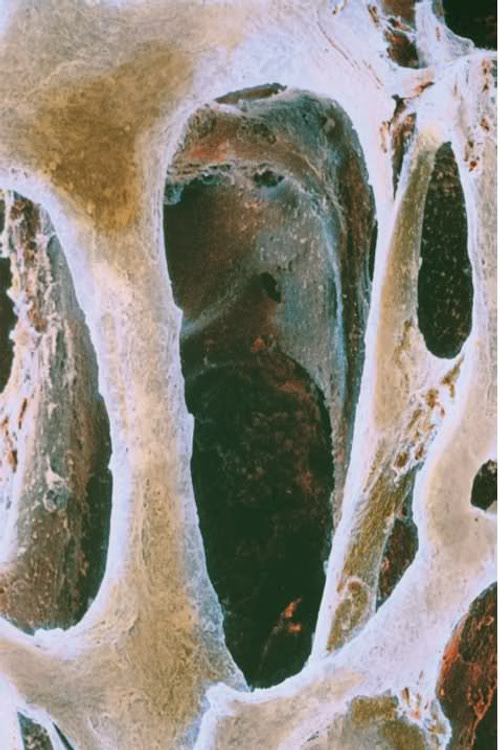

L’osteoporosi è uno delle conseguenze riconosciute della celiachia, e fino ad oggi si pensava che il motivo di ciò fosse la scarsa capacità dell’organismo di assorbire e sintetizzare il calcio e la vitamina D.

La ricerca invece ha scoperto che nel 20% dei pazienti celiaci testati si producevano anticorpi che attaccano una proteina chiave nella salute delle ossa, l’osteoprotegerina.

L’osteoporosi è uno delle conseguenze riconosciute della celiachia, e fino ad oggi si pensava che il motivo di ciò fosse la scarsa capacità dell’organismo di assorbire e sintetizzare il calcio e la vitamina D.

La ricerca invece ha scoperto che nel 20% dei pazienti celiaci testati si producevano anticorpi che attaccano una proteina chiave nella salute delle ossa, l’osteoprotegerina.

Ecco spiegato quindi il motivo per cui è così comune la complicazione di osteoporosi nei pazienti celiaci.